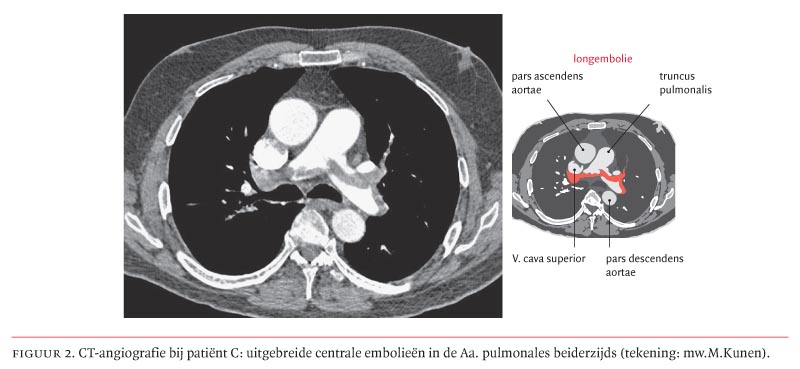

Een longembolie geeft pijn en hevige kortademigheid. Dat merk je doordat je kortademig en benauwd wordt. Bij een longembolie blokkeert een bloedpropje/embolus, de. Om de bloeddoorstroming van de longen te beoordelen. Longembolie hoort daarom altijd in de differentiaaldiagnose te staan bij plotseling ontstane dyspneu, maar ook bij onverklaarde toename van een al langer bestaande dyspneu. Bij een longembolie wordt een longslagader afgesloten, meestal door een bloedstolsel. Een longembolie is een vervelend en gevaarlijk medisch probleem. Het reist naar een longslagader waar het plotseling de bloedstroom blokkeert. De longslagaderen zijn de bloedvaten die van het hart naar de longen lopen. Dit wordt meestal veroorzaakt door een bloedstolsel (trombus). Deze techniek heeft een zeer hoge sensitiviteit en specificiteit voor de diagnose longembolie. Bij een longembolie blokkeert een bloedstolsel de longslagader, waardoor een gedeelte van de longen geen bloed meer. De ct bevestigt een kleine longembolie.